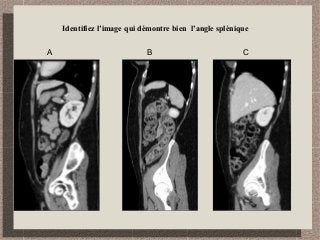

Identifiez l’image qui démontre bien l’angle splénique

A B C

B